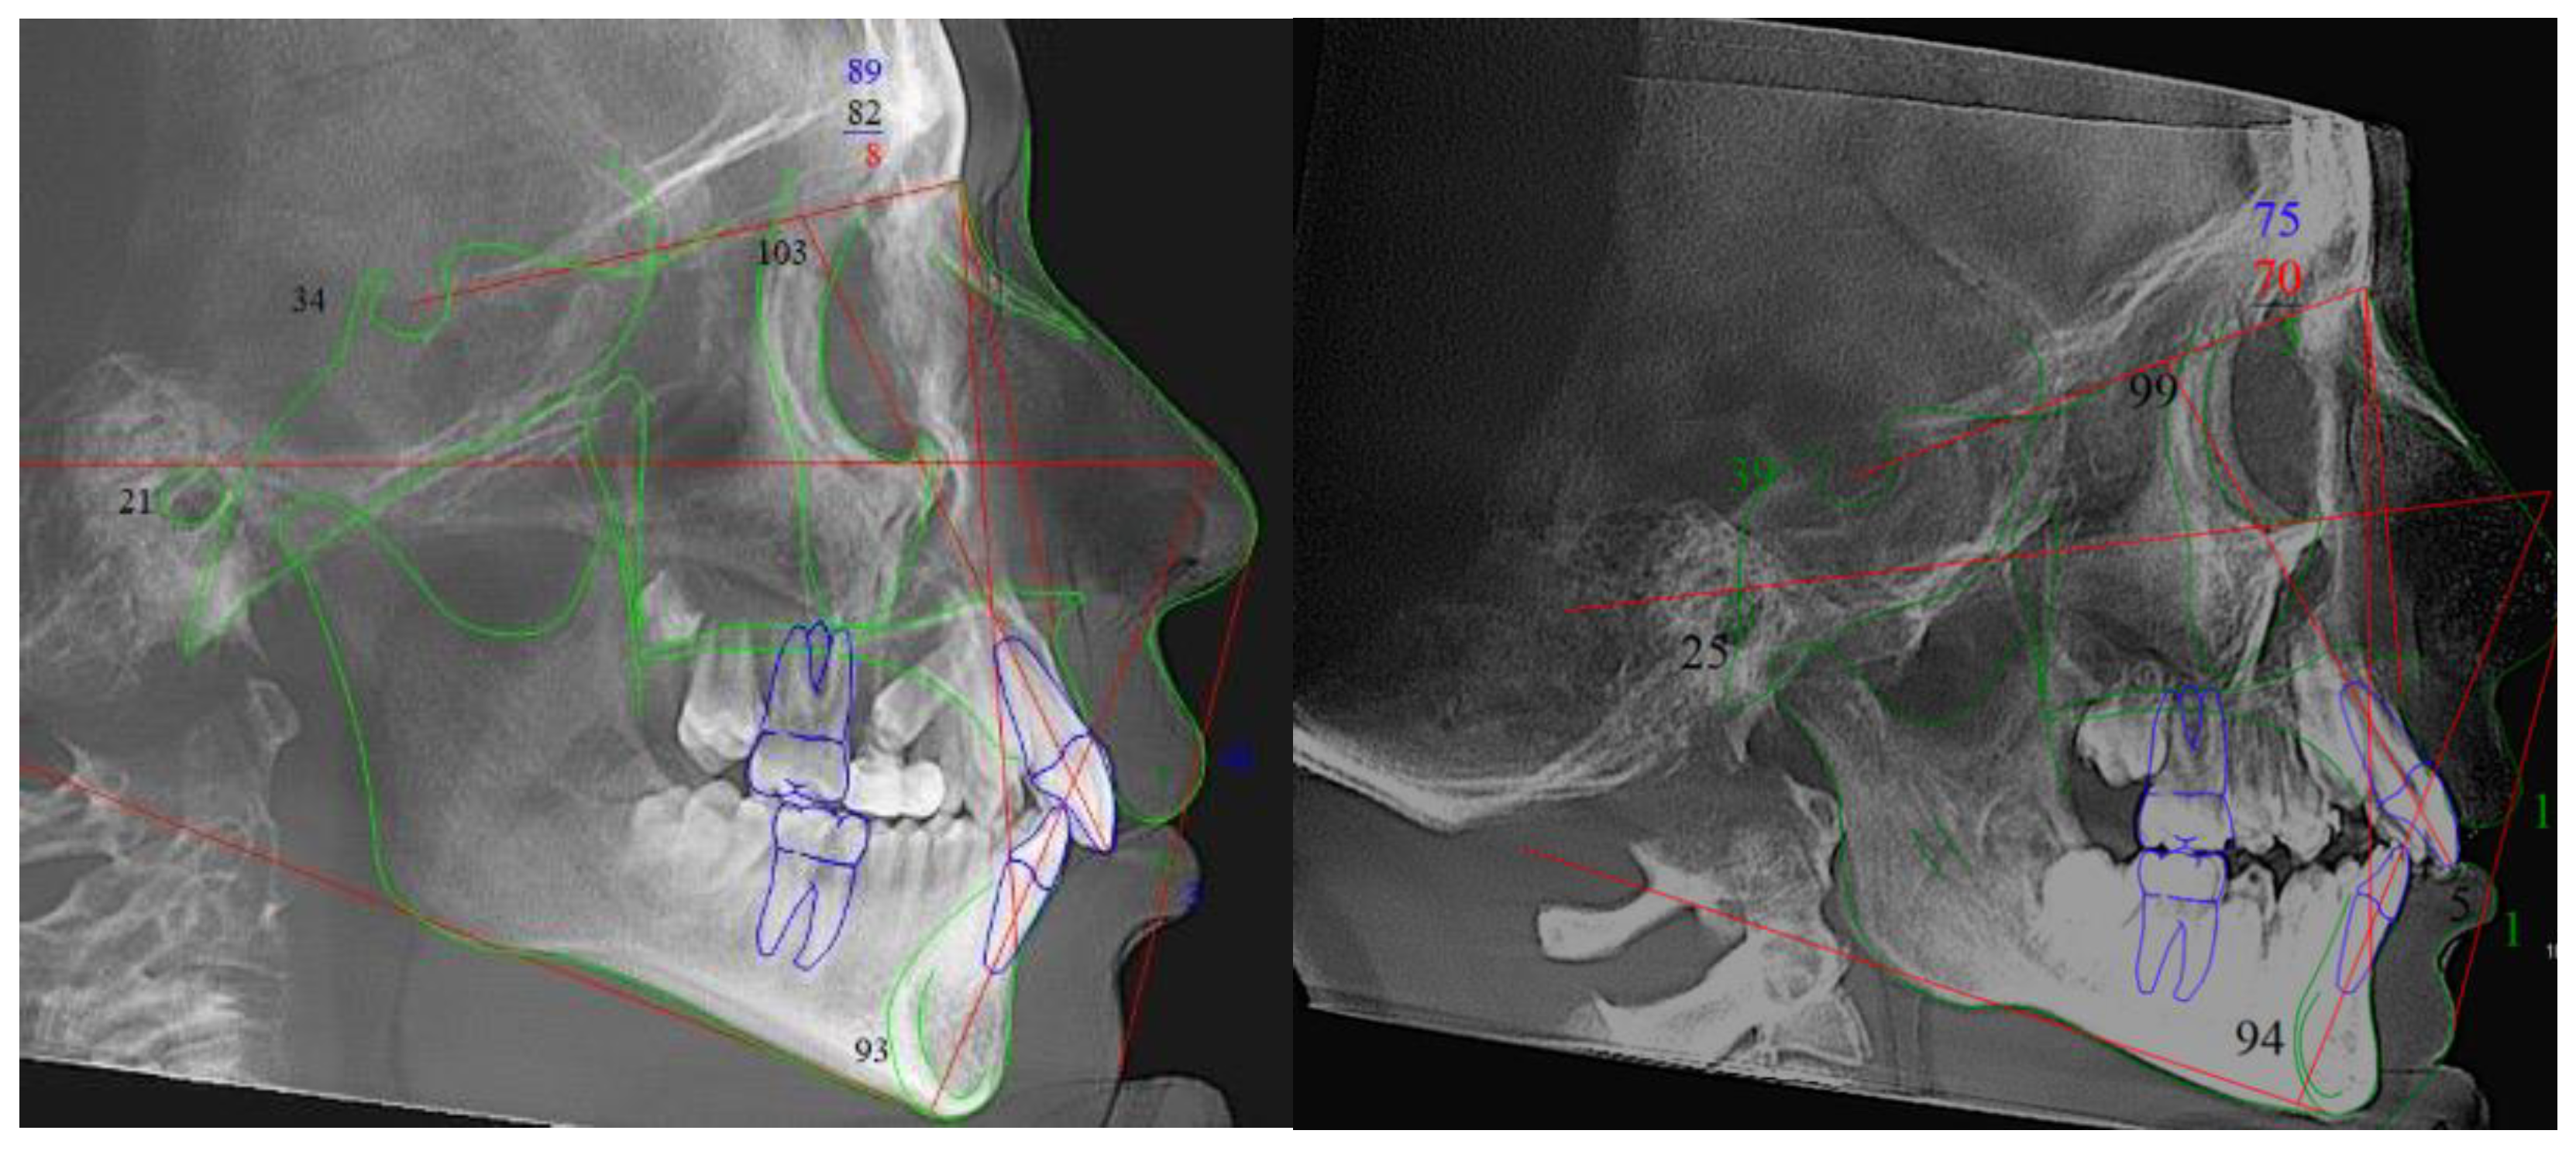

2.2. Cephalometric Rendering and Analysis